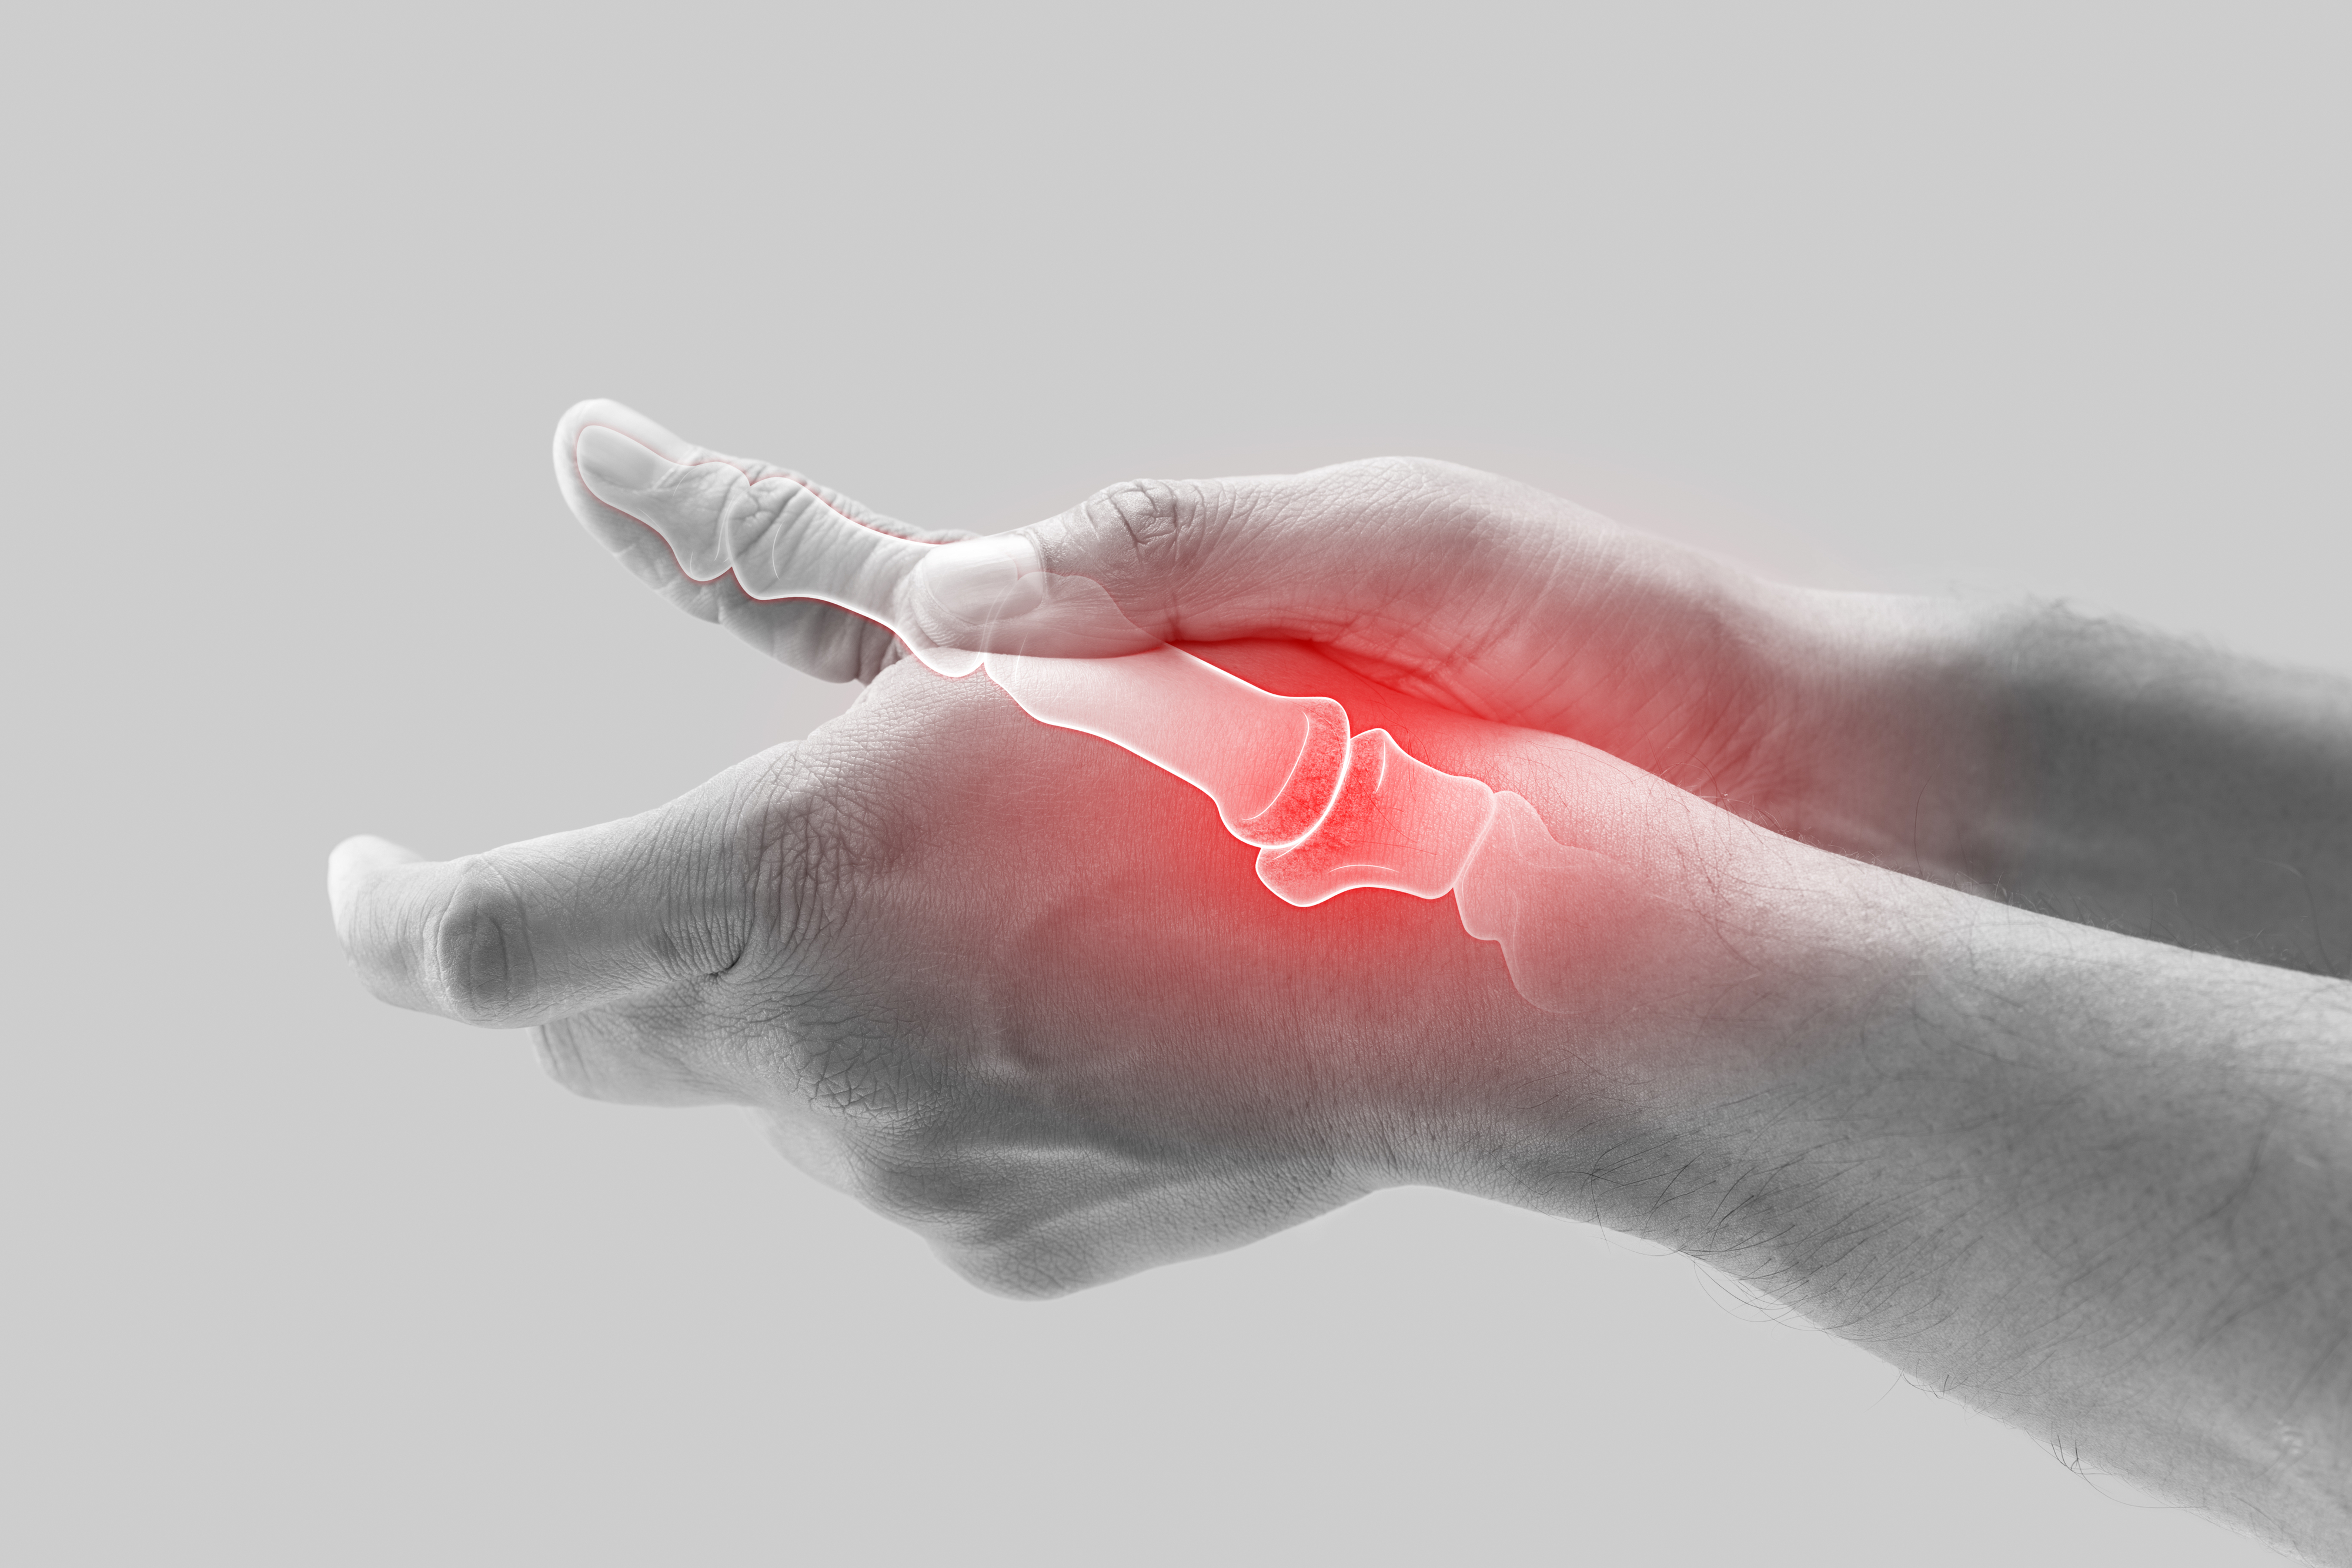

21.“Thumbs. I am a right-handed person. I always tried to be semi-ambidextrous. Got arthritis in my right hand, starting with thumb. Cant grab anything now. Had to learn to do everything but write lefty.”